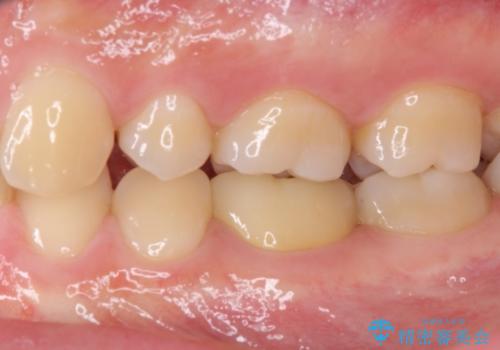

神経近くにまで及んだ大きなむし歯のセラミッククラウン

- 下顎左右奥歯に虫歯で痛みを感じるとのことで来院された患者様です。

むし歯が大きく、神経を取り除く可能性があることを理解いただいた上で虫歯を取り除き、その後はオールセラミッククラウンにて補綴することとしました。

虫歯除去後に痛みは収まり、神経も保存することができました。

変色していた歯もセラミッククラウンで自然な色合いとなり、患者様には大変満足していただきました。